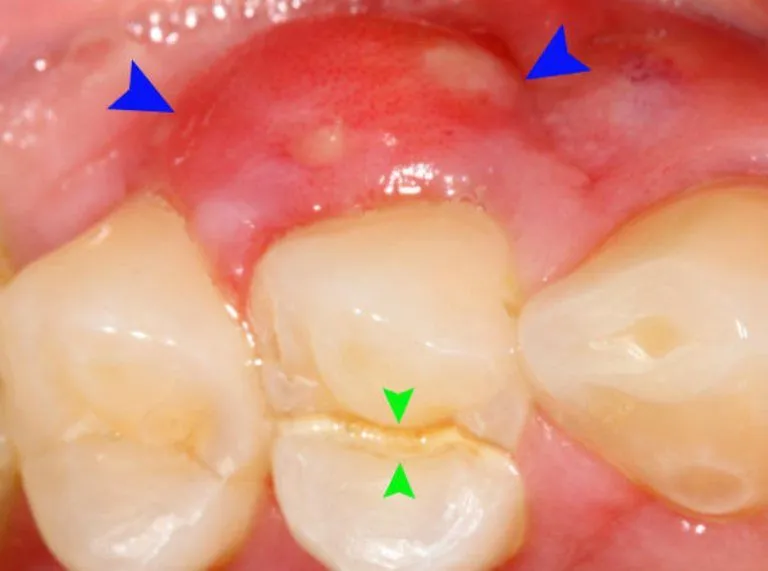

Tình trạng bị sưng lợi chân răng không còn xa lạ với nhiều người, từ trẻ em đến người lớn. Mặc dù đôi khi chỉ là một

Viêm lợi răng hàm không phải là hiện tượng hiếm gặp. Người lớn và người cao tuổi có nguy cơ cao hơn do thói quen ăn uống,